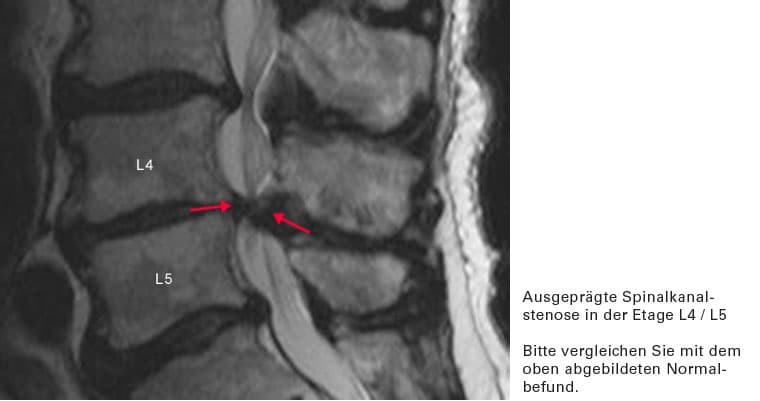

Es liegt eine krankhafte Verengung des Wirbelkanales vor (Stenose des Spinalkanales). Diese tritt in der Regel erst in höherem Alter auf. Sie wird verursacht durch:

• eine sich breitbasig vorwölbende Bandscheibe

• eine Verdickung des Bandapparates, welcher den Wirbelkanal auskleidet

• Verschleiß von Wirbeln und Wirbelgelenken, die knöcherne Anbauten entwickeln, welche in den Wirbelkanal hineinragen

Durch den zunehmenden Bandscheibendruck beim Gehen wölbt diese sich weiter in den Wirbelkanal vor. Die vorbeiziehenden Nerven werden „in die Zange genommen“, die Beschwerden treten auf.